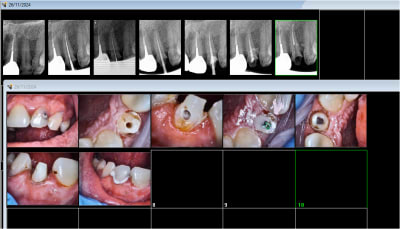

Revenons au cas clinique en mettant de côté le pognon .

Tu as dit en te moquant " c est certainement occlusal "

Eh sûrement que le point de départ est occlusal , à mort :-)

A commencer par la mort de la 14 :-)

Bin oui , pcq tu parles d endo de 12 , 13 , 15 , 16 , 17

et là 14 , elle n a rien ? :-))

et comme il y a un pb de point de contact en distal + et en mesial+++ sur la 15 ,

J en déduis que c est une classe 2 avec extraction des 4.

Alors ,une classe 2 après extraction et ortho , avec toutes les dents dévitalisée et couronnées sur un secteur entier , s il n y a pas eu un pb occlusal , c est un miracle .

Elle lui dit , j ai mal de ce côté.

Et sûrement que vous ayez mal :

- entre la 6 et la 7 , y a le gouté pour le 4 heure , en plus y a la céramique cassée en arrière de 6 .

Pas grave la 7 est foutue faut l enlever et après vous referez la couronne de 6 .

- et la 15 et la 13 , faut reprendre l endo .

Elle a refait faire la 15 et la 13 , et rien d autre et tu la reçois